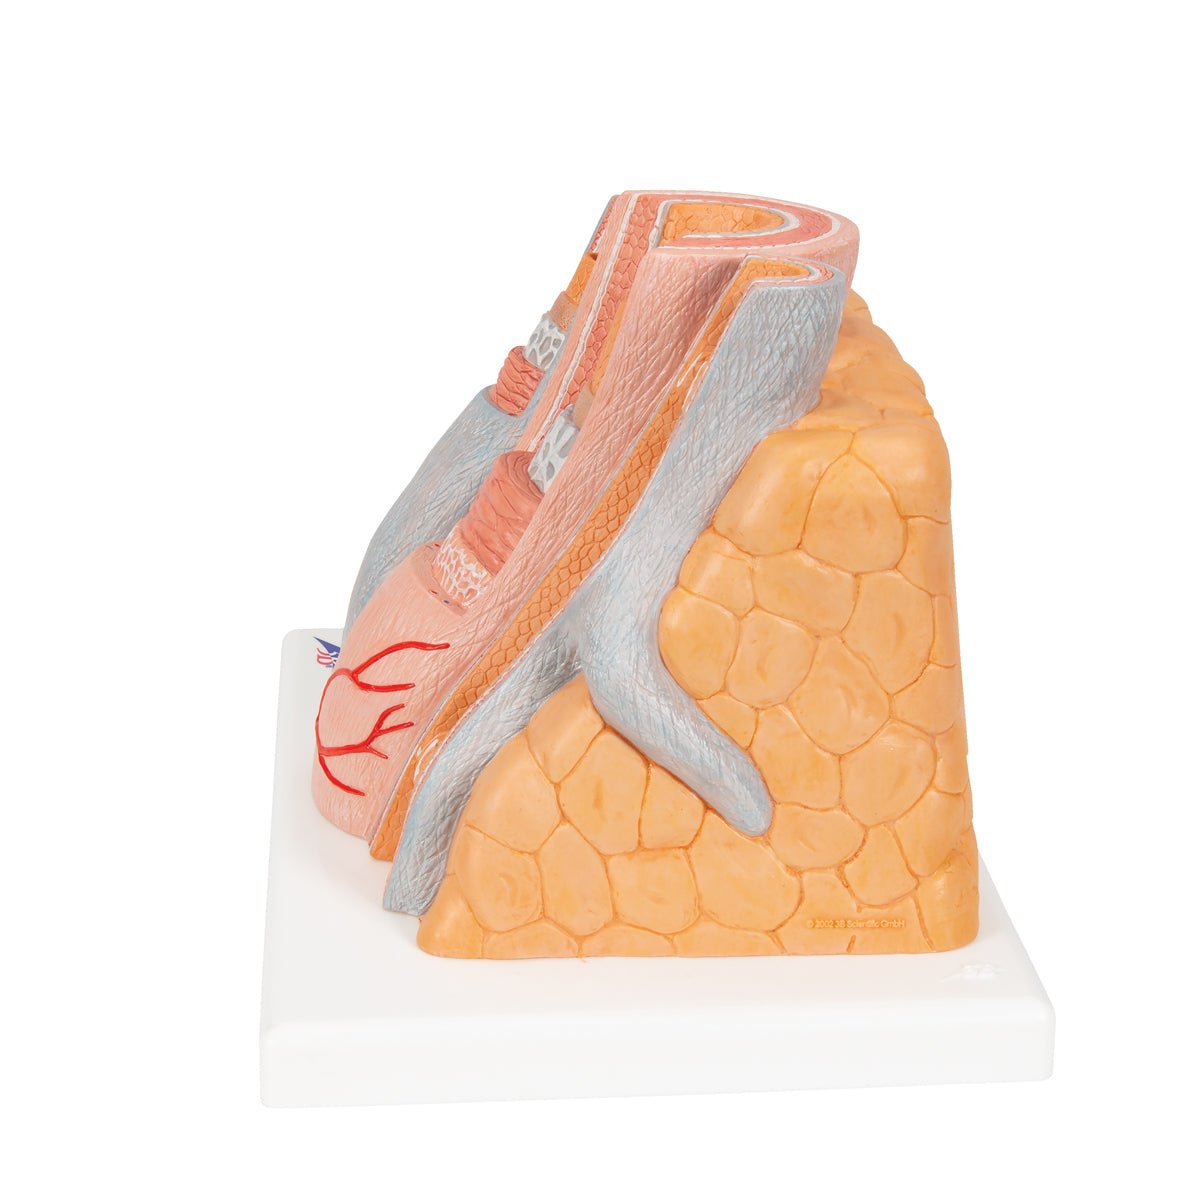

Salg af anatomiske modeller er det bærende element i eAnatomi, selvom vi også bruger mange ressourcer på at udvikle vores egne anatomiske materialer som fx plakater. Anatomiske modeller anvendes til forskellige formål og kan både vise afgrænset væv, organer samt organsystemer. Søger du en simpel model af knoglevæv eller måske en avanceret torso-model baseret på MRI teknologi, kan du finde det hele på eanatomi.com.